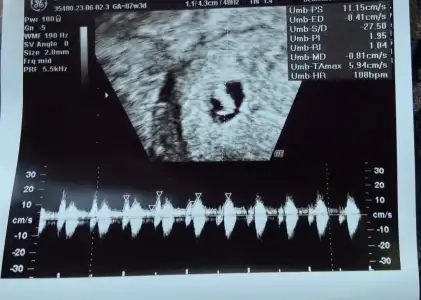

Selam kızlar geçen cuma gittiğimde sadece kese ve yolk vardı 4+6 demişti az önce gittim bebek 6+1 kese 5+0 dedi yanında boş kese var gibi bide dedi kese geçen haftaya göre büyümemiş yani ama kalp duyduk takip edecez dedi böyle olup devam edebilir mi acaba sağlıklı

Evet ikinci fotoğrafta yüzük gibi olan yerde iki kese var dedi o büyümesini engelledi sanırım hayırlısı bakalım ya inşallah sende duyarsın kalbi